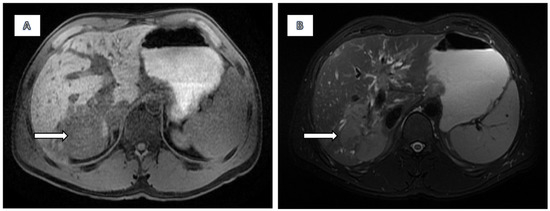

2.2. Imaging